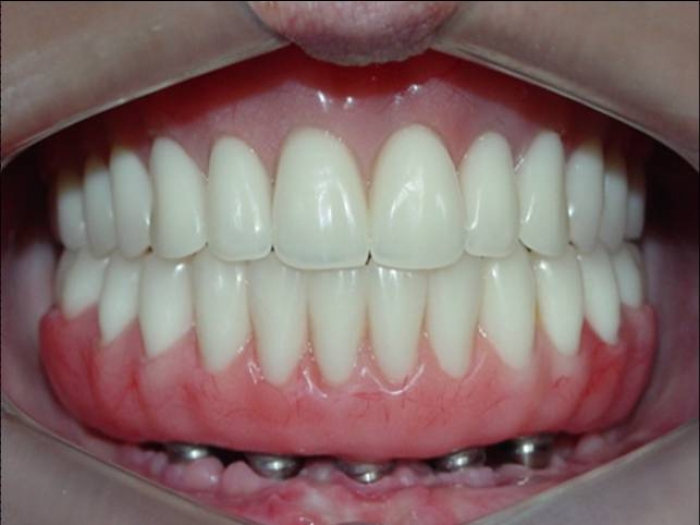

Prótese fixa sobre implantes inferior e nova prótese superior

Sorriso final do caso terminado em abril de 2012